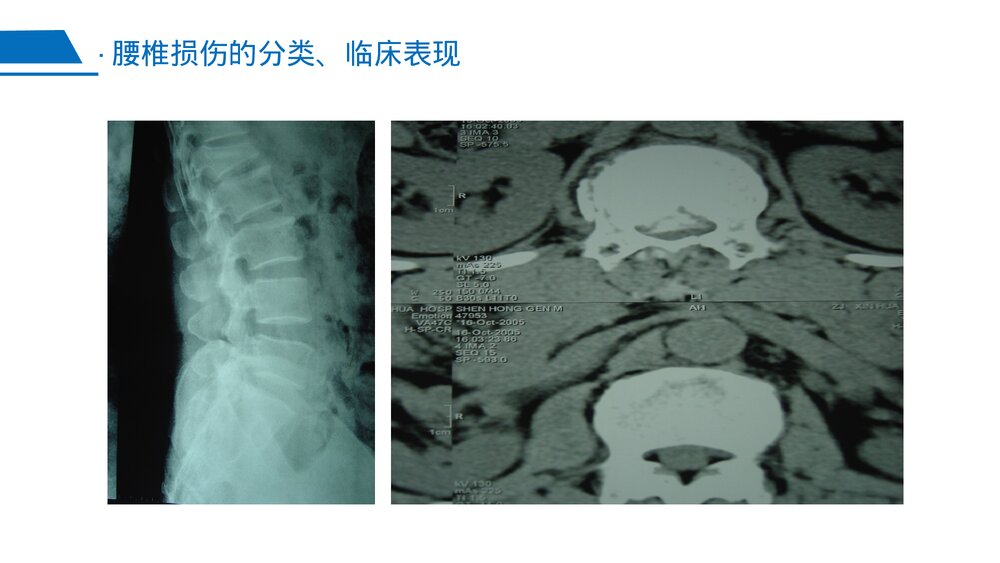

腰椎骨折汇报人:XX时间:XX年XX月XX日LOGO202x脊柱的解剖与功能1腰椎的生理特点2腰椎损伤的主要病因3腰椎损伤的分类、临床表现4治疗5腰椎骨折的围手术期护理6·CONTENTS脊柱的解剖与功能历史上,脊柱的姿势已通过艺术的方式被记录下来。早期的艺术家们描述脊柱柔和弯曲的美丽的外观来表现躯体的优美姿势,同时亦为了某种目的常夸大了脊柱的畸形。脊柱包括7节颈椎,12节胸椎,5节腰椎,5节融合的骶椎和3-4节融合的尾骨节段·脊柱的解剖与功能脊柱的解剖与功能·脊柱的解剖与功能脊柱具有传导载荷,运动和保护重要的脊髓和马尾神经三个基本功能。它从骨盆后方的基底部向上延伸到最高点,在那儿它作为头颅的支撑点。骶骨既是脊柱的一部分又是骨盆地一部分,胸椎是胸廓不可缺少的组成部分。脊柱的其他两部分,腰椎和...